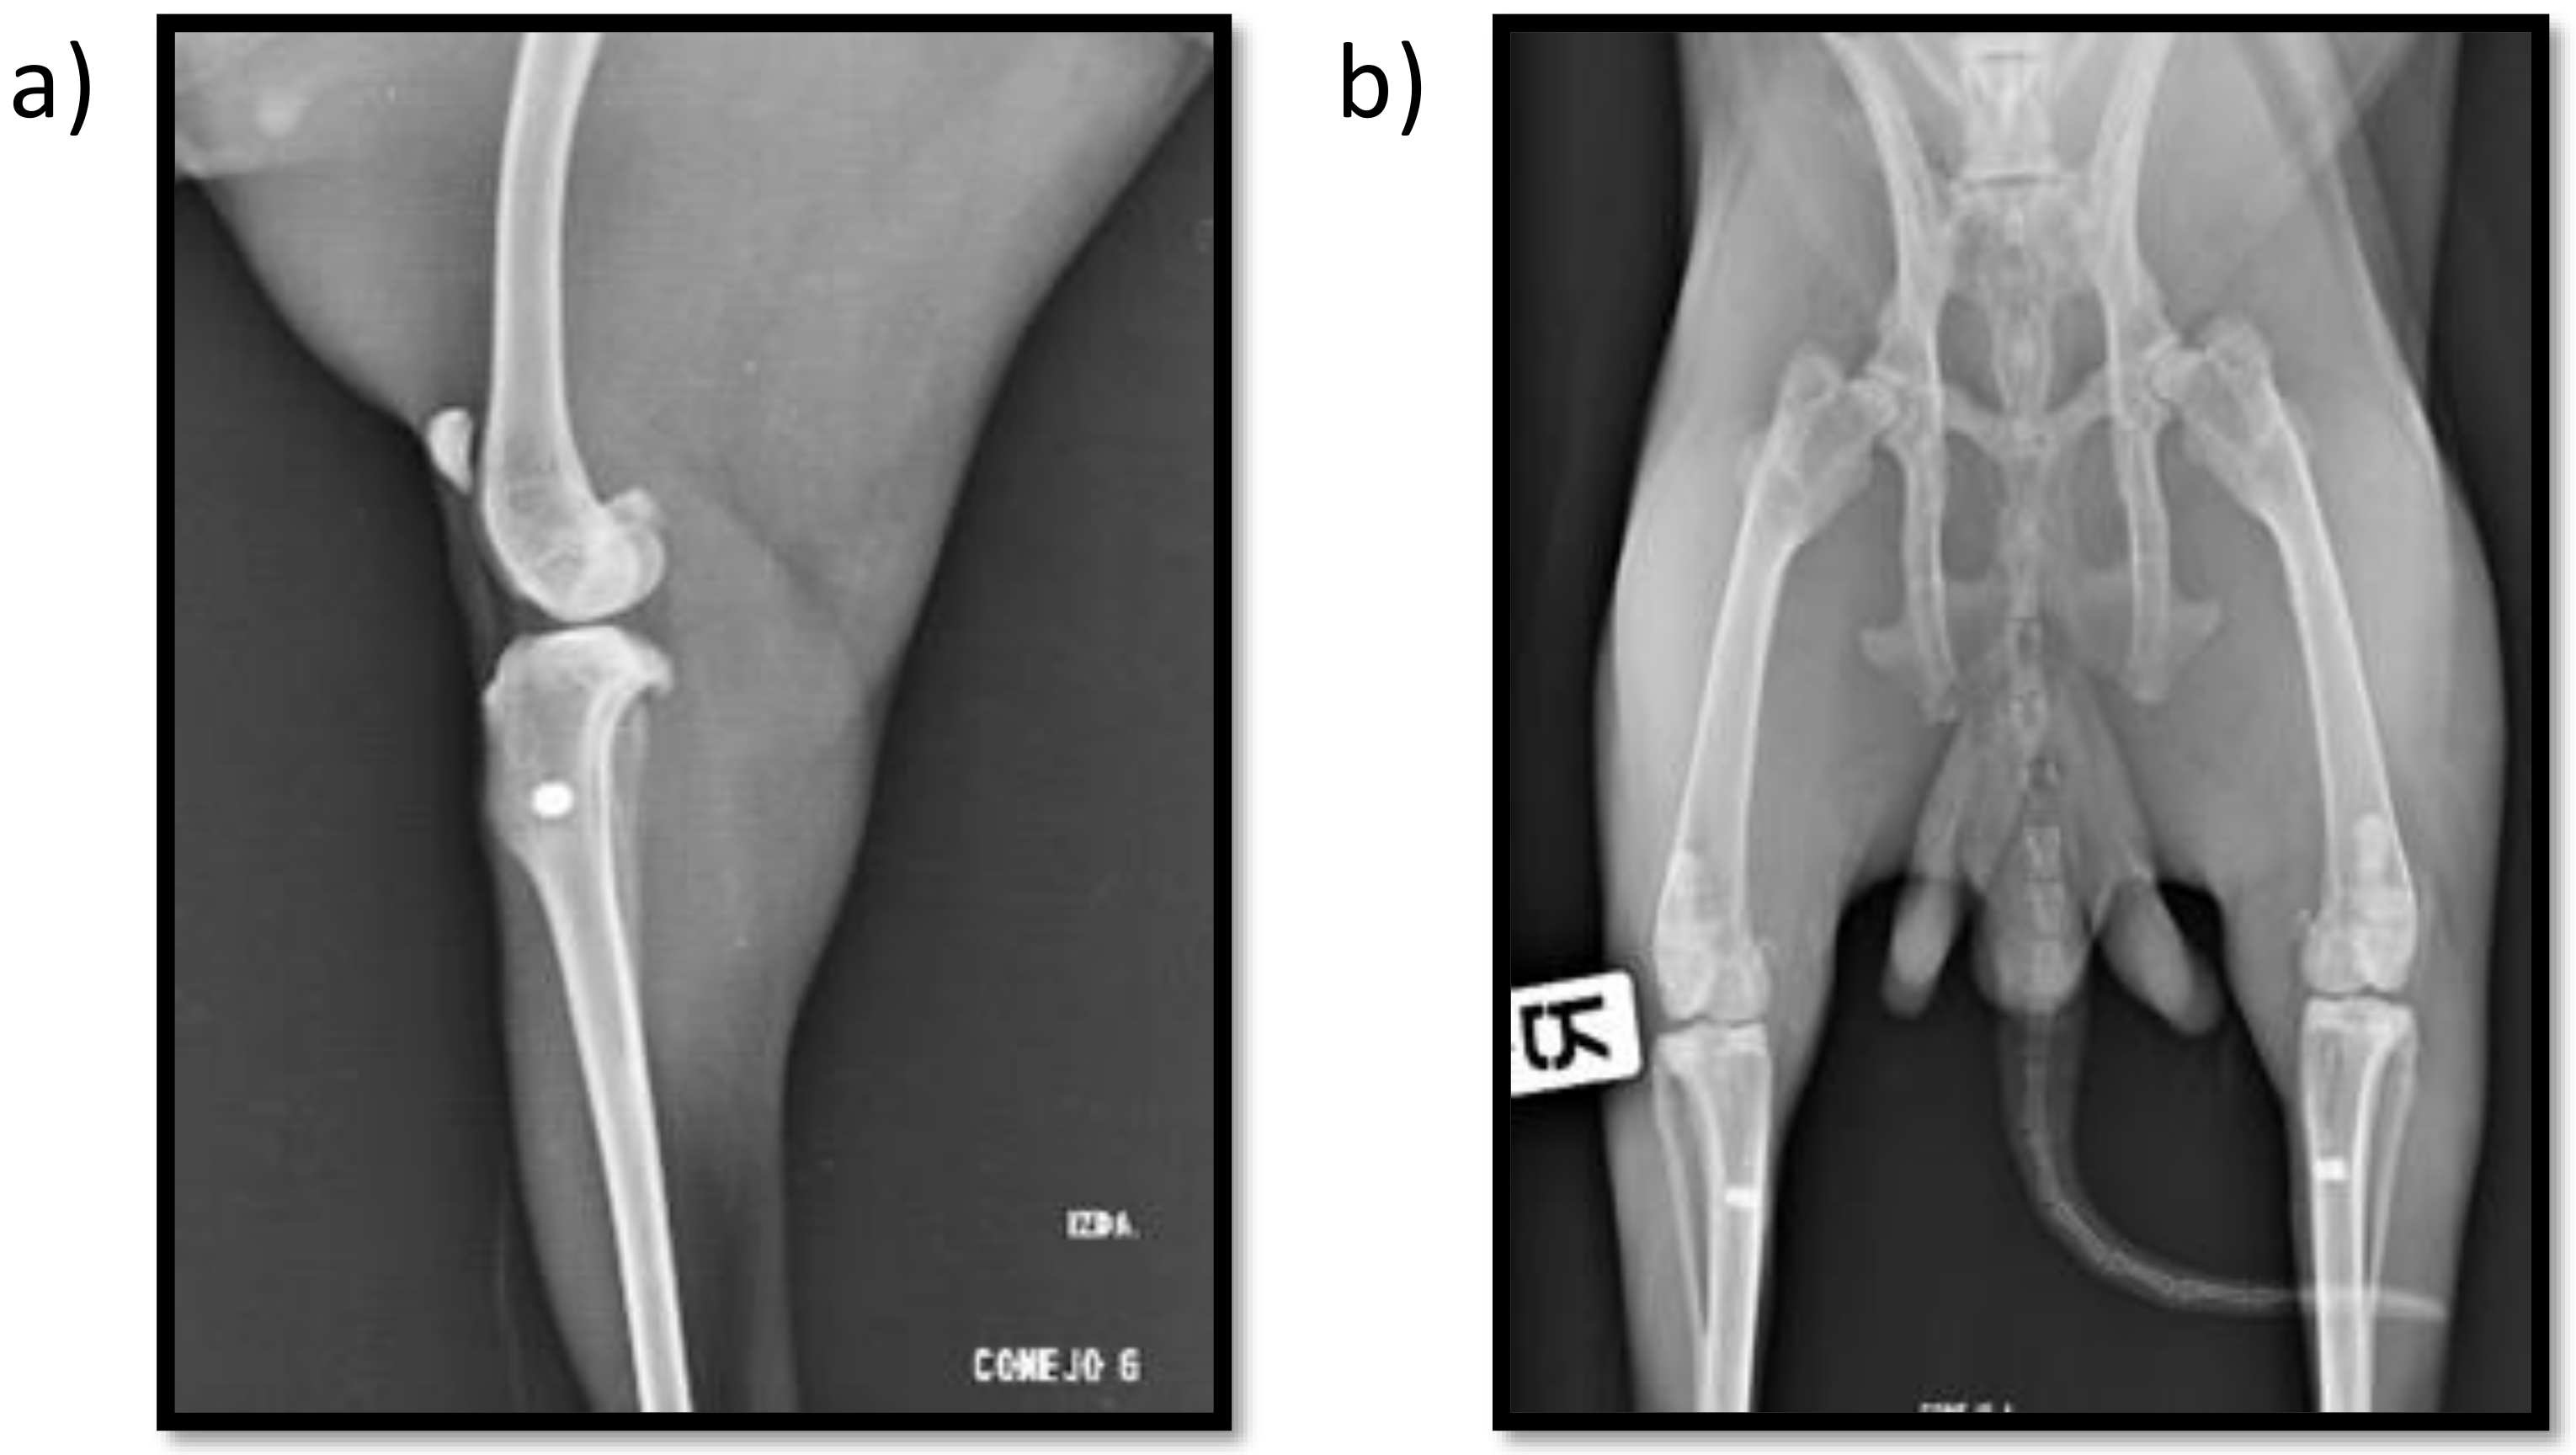

Postoperative radiographs show the proper placement of the titanium implanted cylinders (Figure 1). The radiographic evaluation of the isolated tibiae at the end of the study also showed all the titanium cylinders to be properly placed, with no signs of implant migration.

Figure 1.

Mediolateral (a) and craniocaudal (b) postoperative X-ray images showing both insertion point location and implant alignment.

Peri-implant radiolucency was not observed in any sample, and good bone-to-implant contact was confirmed radiographically in all the samples, indicating an adequate new bone formation response around the implants.